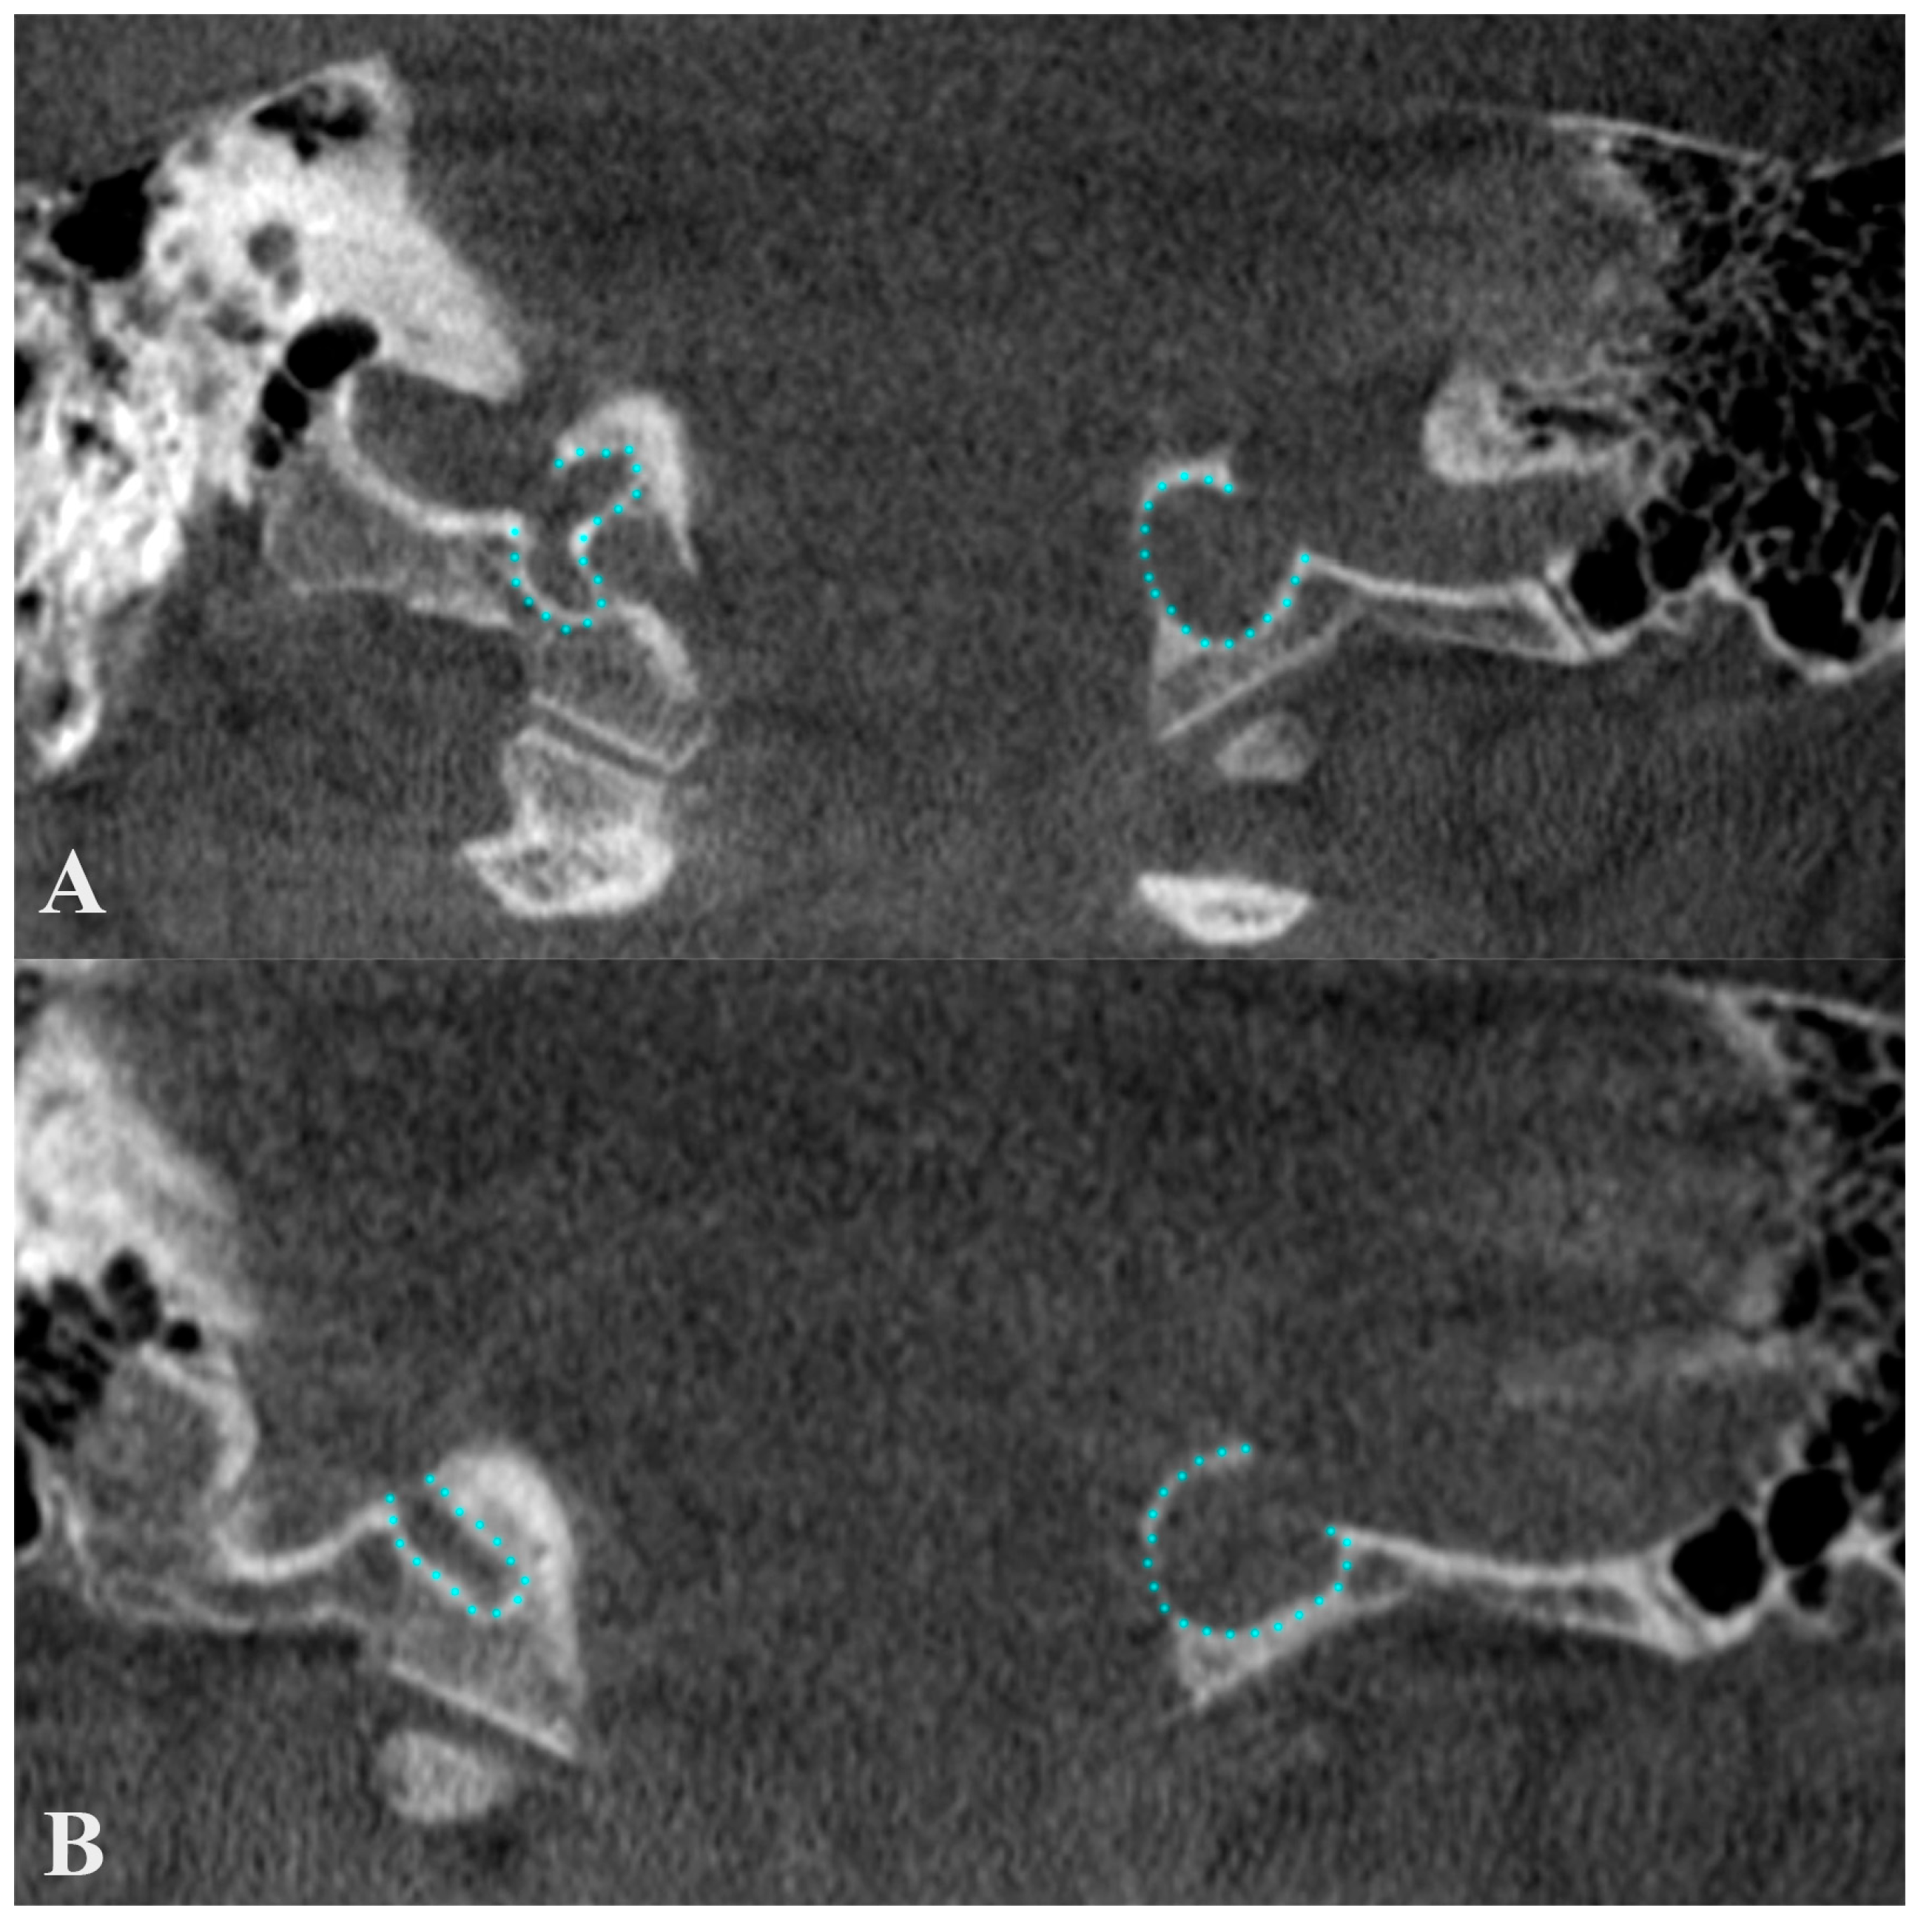

3. Diverticula

The “Condylar Jugular Diverticulum”: True or False?